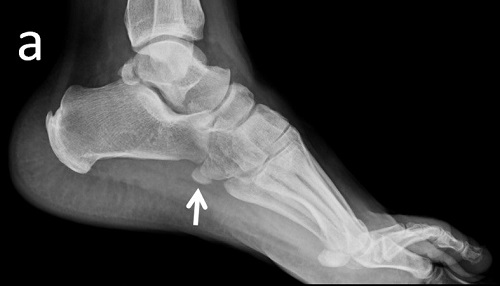

Niña de 11 años de edad sin antecedentes de interés que acude a Urgencias por dolor a nivel del maléolo externo del miembro inferior derecho tras un movimiento anómalo del pie con inversión del tobillo hace 2 días. Asocia tumefacción e impotencia funcional leves. Le han administrado analgesia en el domicilio sin mejoría. A la exploración, presenta tumefacción y dolor selectivo a la palpación del maléolo externo y los ligamentos peroneoastragalinos anterior y posterior. No crepitación ni resaltes óseos ni hematoma. No presenta limitación de la movilidad pasiva y si presenta limitación a la movilización activa por dolor. Se realiza radiografía anteroposterior (Figura 1) y lateral (Figura 2) del tobillo derecho.

Figura 2. Proyección lateral.